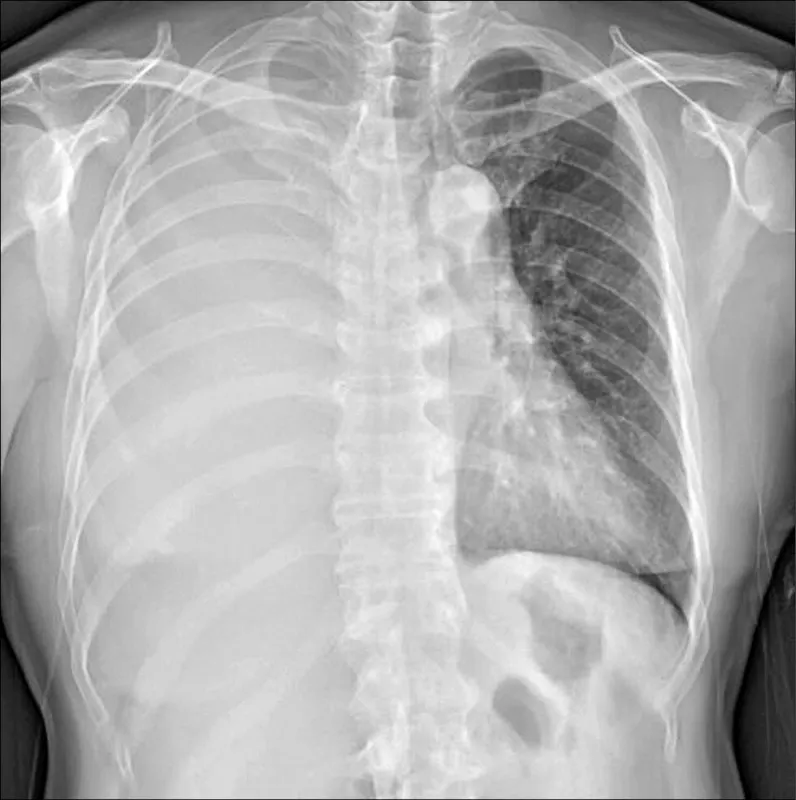

〈病症六行詩: 惡性肋膜間皮瘤〉/小熊